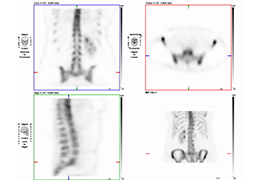

Multi-planar slicing.

Oblique slicing.